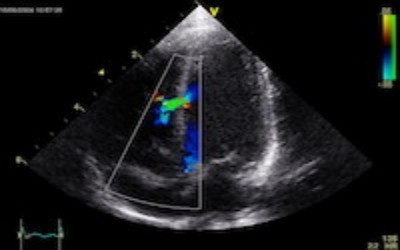

Videoteca em Ecocardiografia